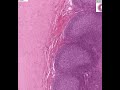

Shotgun Histology Appendix

Video Tags:Appendix, Histology, Shotgun